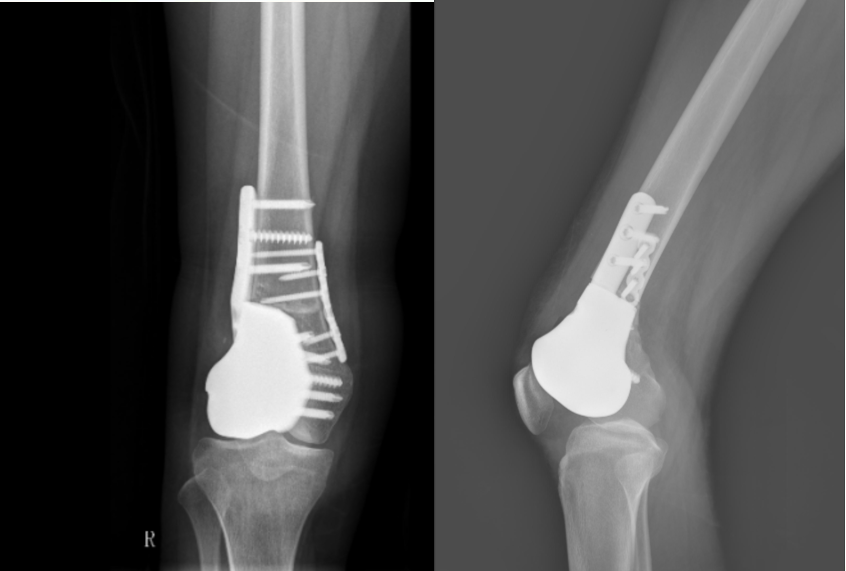

与传统术式相比,该技术优势显著:不仅创伤更小,而且假体设计为骨长入界面,实现了生物固定,更加牢固耐用,有效降低了年轻患者长期使用假体可能出现的远期并发症风险。术后第一天,李女士即可在医生指导下进行股四头肌功能锻炼;术后第五天顺利出院;预计术后4周便可自由活动。

这是该患者术后复查时的影像。